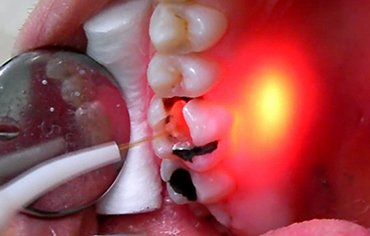

We are introducing the latest innovation in ROOT CANAL TREATMENT incorporating LASER, latest ROTARY EQUIPMENT and DIGITAL RADIOGRAPHY.

LASER ASSISTED ROOT CANAL TREATMENT

• Focussing the bacteria and infected area with greater accuracy.

• Less bleeding and inflammation.

• More precise than traditional method.

• Reduce the discomfort of the patient.

• Prevents reinfection – Because of the efficacy of LASER to reach and clean the accessory canals.

• Better Canal Sterlisation – Atleast 99.7 % reduction in bacterial count.